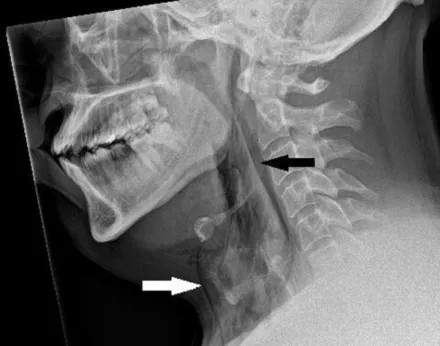

W badaniu RTG bocznej tkanki miękkiej szyi stwierdzono rozedmę chirurgiczną. W tomografii komputerowej szyi i klatki piersiowej z kontrastem uwidoczniono rozdarcie tchawicy o wymiarach 2 mm × 2 mm × 5  mm na poziomie między trzecim a czwartym kręgiem piersiowym, z odmą śródpiersia i rozedmą chirurgiczną szyi" - czytamy.

Uraz tchawicy po stłumieniu kichnięcia/BMJ Case Reports